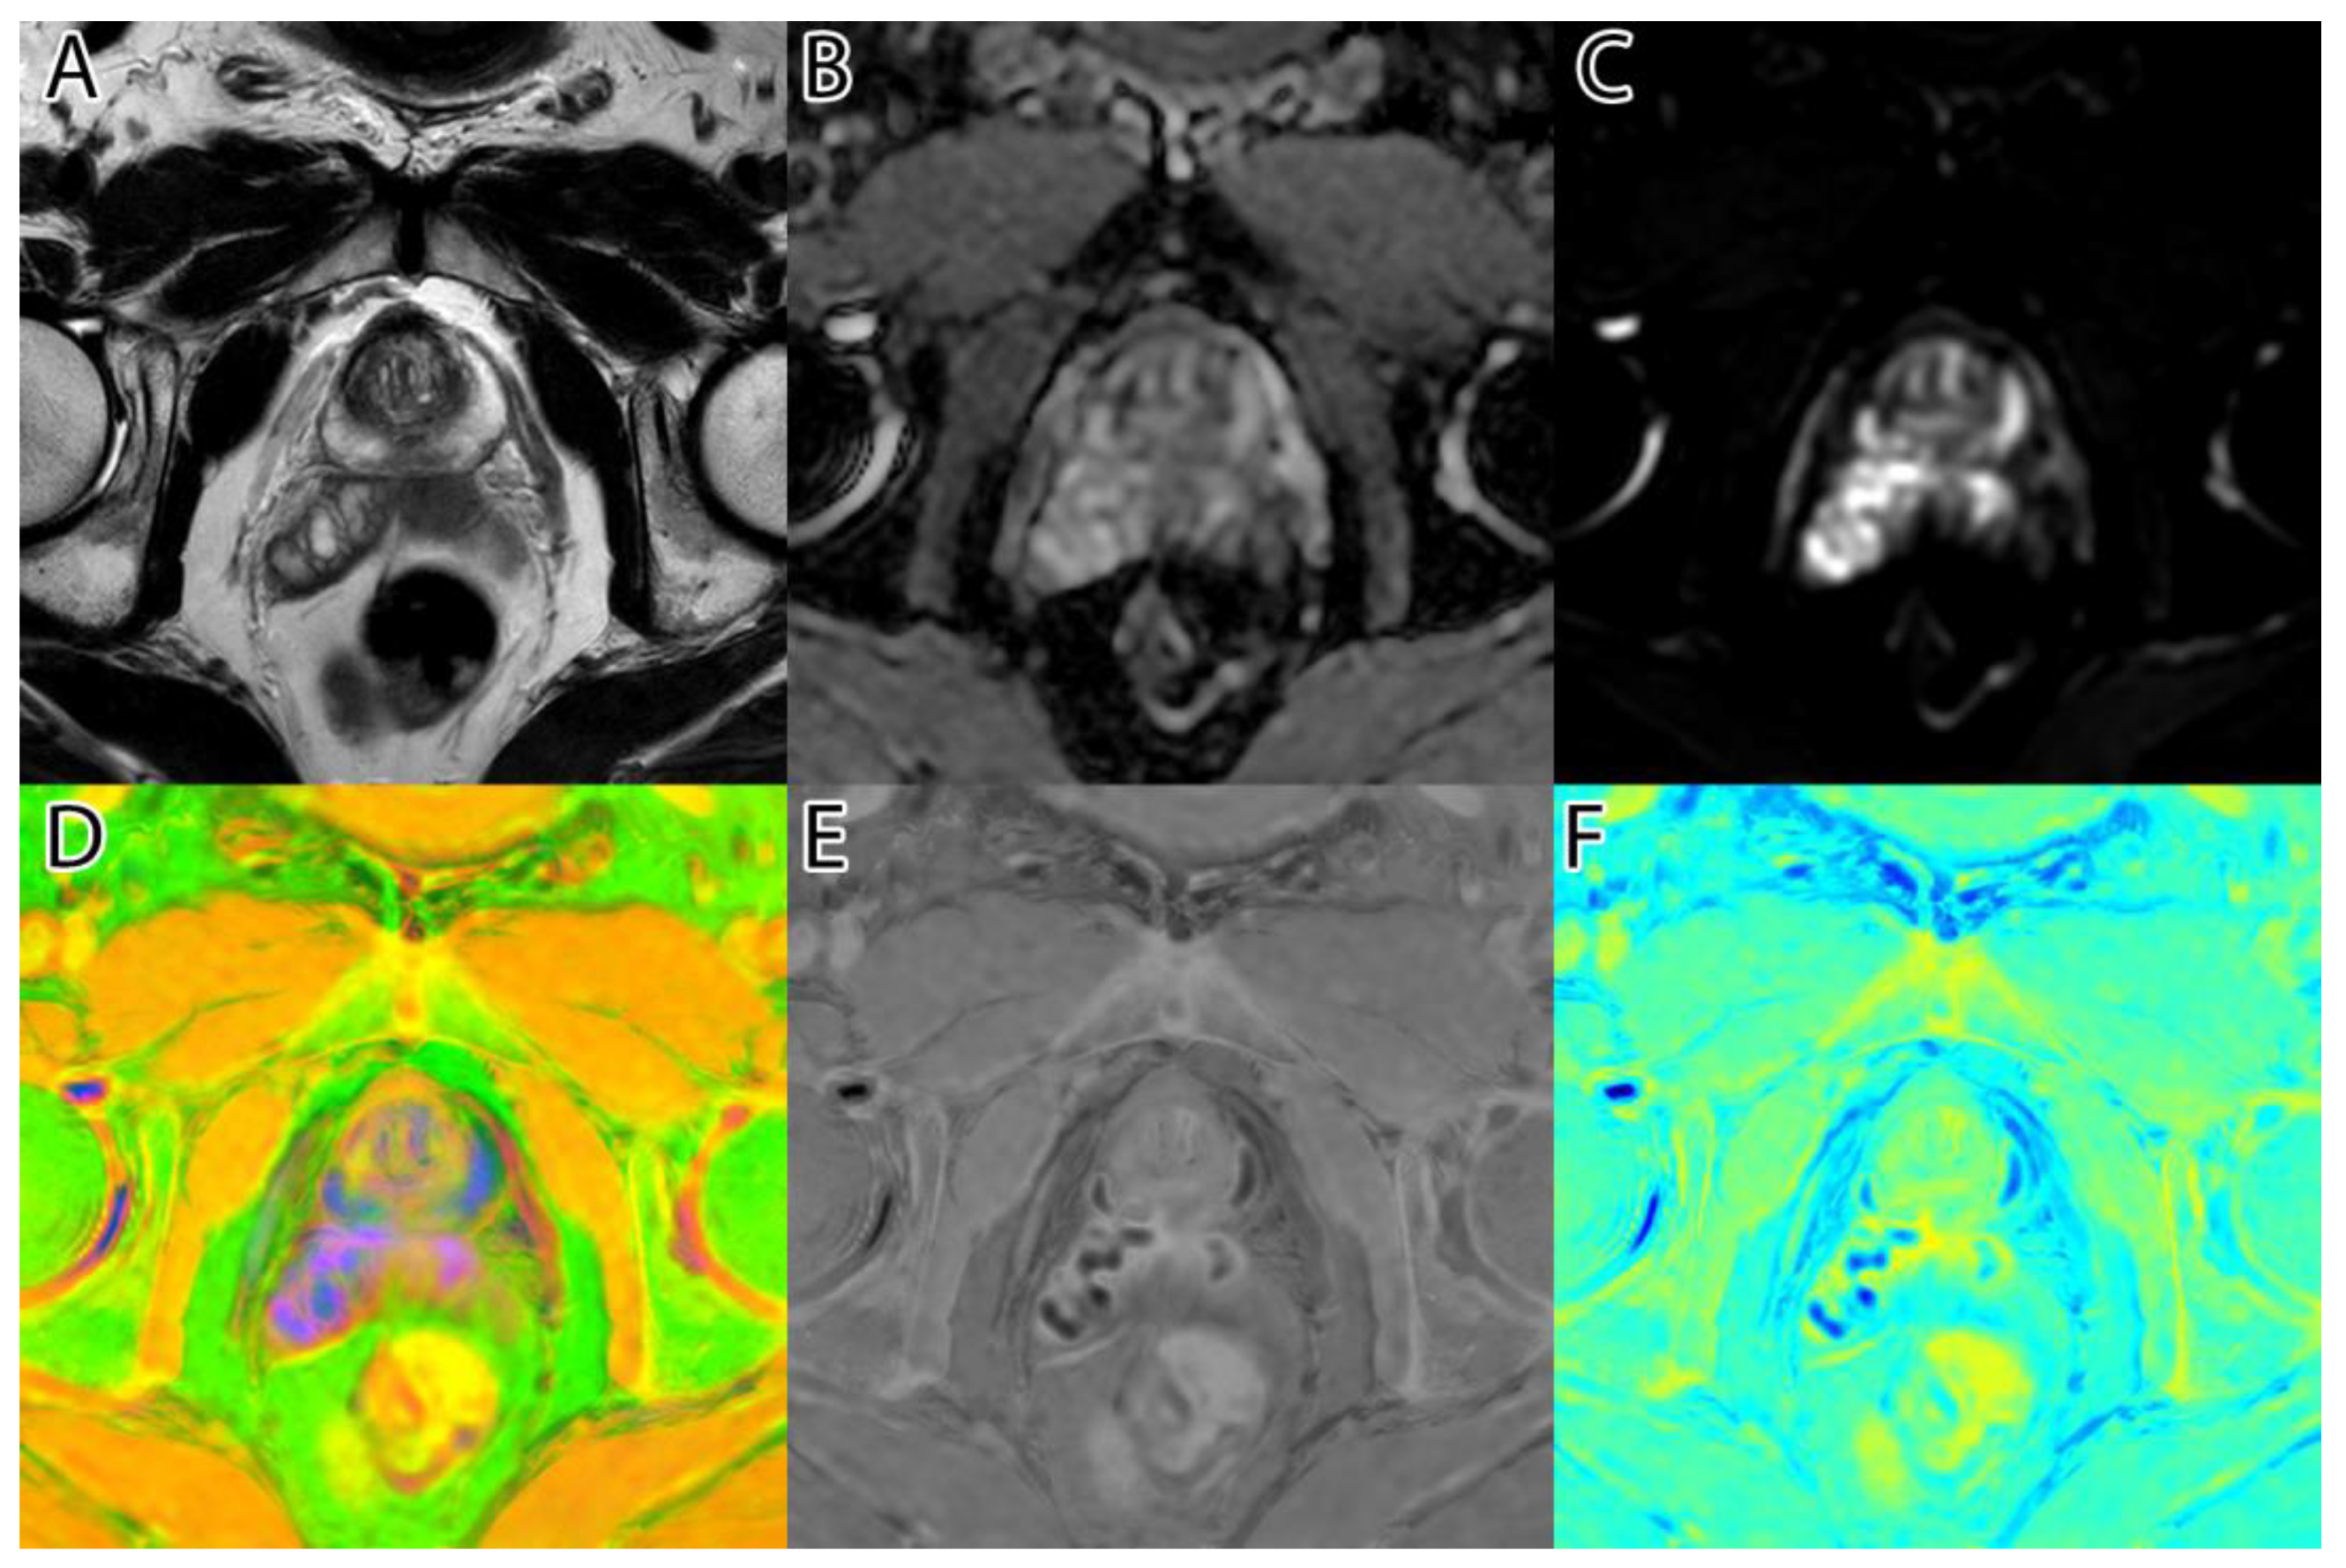

The sixth and final step was to compute the final intensity mask by subtracting the square root from the square sum of the alpha–beta channels and subtracting the resulting value from the luminance. The resulting intensity image can be seen in Figure 2B and Figure 3B. By adding the ‘jet’ color map to it, we obtained a colored intensity map that highlights the tumoral areas, as seen in Figure 2C and Figure 3C.

Figure 3. PI-RADS 5 patient: (A)—T2WI; (B)—ADC; (C)—DWI; (D)—RGB fused image; (E)—grayscale tumor intensity image; (F)—‘jet’-mapped tumor intensity image.

Samples of the computed tumor intensity images can be seen in Figure 2 for a PI-RADS 2 patient and in Figure 3 for a PI-RADS 5 patient. Notice the difference in “jet” intensity between the control patient and the patient with extraprostatic invasion.

In the transitional zone, a lesion with a heterogeneous signal and obscured margins in the T2WI sequence, but not evident in the DWI and ADC sequences, is considered PI-RADS 3. Therefore, superimposing DWI and ADC over it only causes the addition of noise in these cases (Figure 10).

Figure 10. A PI-RADS 3 lesion in the posterior transition zone on the left side surrounded by insignificant areas of diffusion restriction. PI-RADS 3 lesions are only visible on T2WI, so fusion with DWI and ADC does not highlight them: (A)—T2WI; (B)—ADC; (C)—DWI; (D)—the radiologists’ annotation; (E)—grayscale tumor intensity image; (F)—our ‘jet’-mapped tumor intensity image.